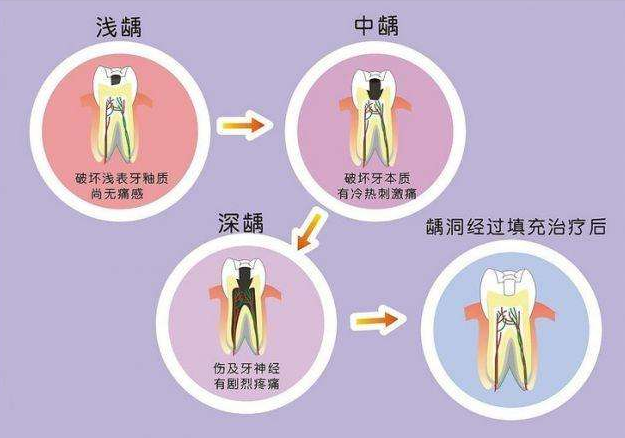

1、深龋

临床表现:冷热刺激一过性疼痛,扣诊、探诊洞底敏感,无自发痛。

治疗方法:找牙医补上即可。

预防方法:好好刷牙,定期找牙医检查。

3、急慢性牙髓炎

临床表现:可有自发性、阵发性、放射性疼痛且不能定位,冷热刺激加重,可有扣痛或不适。慢性牙髓炎可有长期牙痛史,多可定位患牙,稍有扣痛或不适。

治疗方法:根管治疗杀神经,做牙套。

预防方法:好好刷牙,定期找牙医检查。